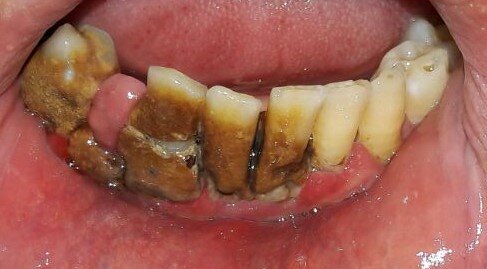

Descriviamo il caso di un paziente maschio di 56 anni con diagnosi di parodontite moderata generalizzata (Figg. 1-3), affetto da Diabete Mellito II in fase di scompenso (HbA1C 8,4%). Oltre alla malattia diabetica diagnosticata da 12 anni, il paziente presentava in anamnesi insufficienza renale, pregresso infarto miocardico acuto e storia di ipertensione arteriosa. I dati anamnestici hanno guidato la scelta dell’iter terapeutico da parte del team odontoiatrico.

In sede di valutazione clinica, il paziente presentava una scarsissima igiene orale e si evidenziavano evidenti segni di flogosi gengivale a causa di notevoli depositi di tartaro sopragengivale e sottogengivale, che rendevano difficoltoso un accurato esame parodontale. Successivamente, si è proceduto alla discussione in team circa la necessità di un intervento terapeutico personalizzato ed efficace che prendesse anche in esame la scarsa disponibilità emotiva e psicologica del paziente ad affrontarlo. Nel presente caso clinico l’adherence è stata considerata come un processo in continuo divenire. Adottando un approccio mutuato dal metodo biopsicosociale5 in una fase preliminare, un primo colloquio è stato svolto con il coniuge del paziente, al fine di instaurare un percorso riabilitativo di salute orale che fosse supportato anche dal caregiver.